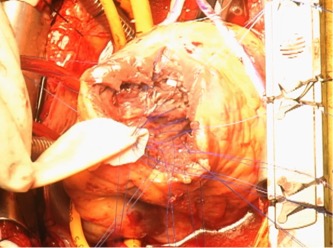

心室中隔穿孔に対するInfarct exclusion法の一部

左室形成術(オーバーラッピング法)